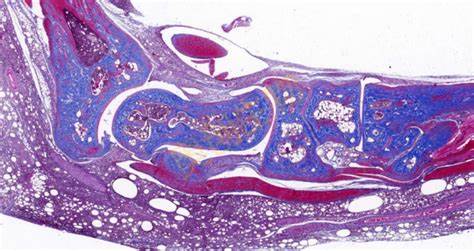

免疫组化(Immunohistochemistry,IHC)是一种利用抗原 - 抗体特异性反应来定位和定性组织细胞中特定抗原的技术,在病理学、肿瘤学等众多领域发挥着关键作用。**一、原理**1. 抗原 - 抗体反应 - 基于抗原与抗体之间的高度特异性结合。组织细胞中的蛋白质、多肽等抗原成分能够被相应的特异性抗体识别并结合

400-9929-003 立即咨询免疫组化(Immunohistochemistry,IHC)是一种利用抗原 - 抗体特异性反应来定位和定性组织细胞中特定抗原的技术,在病理学、肿瘤学等众多领域发挥着关键作用。

特殊染色是病理学和组织学中使用的一种染色方法,用于显示组织或细胞中的特定成分,这些成分在常规的苏木精 - 伊红(HE)染色中可能无法清晰地显示。以下是关于特殊染···...